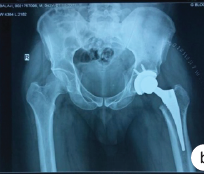

Hip Abduction Strength Assessment and its Effect on Functional Outcome Following Hip Arthroplasty – Original Article

B Vishnu Vardhan , P Pradeep , B Raghavendran , U Thiyagarajan , M Rayeez Ahmed

………………………………p.322-328